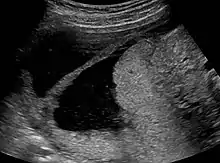

![]() | |

| Ultrasound view. | |